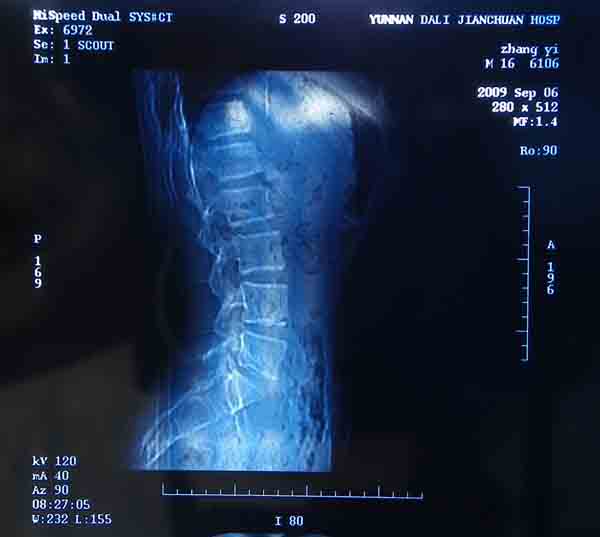

腰5/骶1椎间膨突出外,还有点异常,不知是什么东东,请各位大虾帮忙看看(12骨窗最明显)